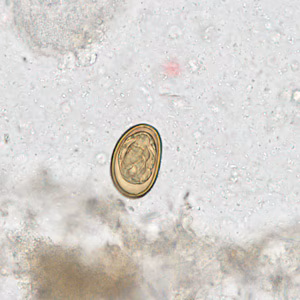

Case #281 – August, 2010

A twenty-year-old male from India presented with recurrent abdominal pain. He underwent an appendectomy at a local medical center. Sections of the appendix were obtained, sectioned, and stained with hematoxylin and eosin (H&E). Figures A–D show what was observed microscopically. What is your diagnosis? Based on what criteria?

Figure B